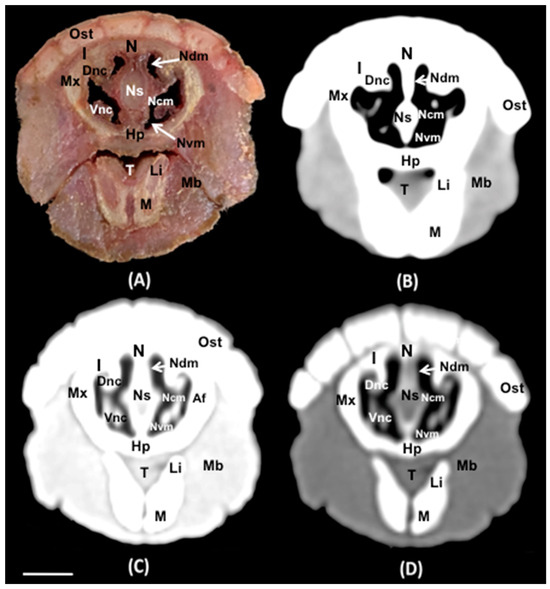

3.1. Anatomical Sections

3.2. Computed Tomography (CT)